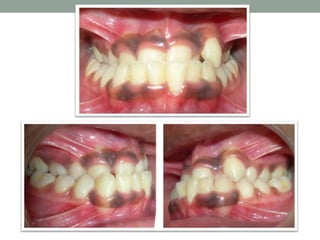

• Anterior crossbite is defined as the malocclusion that results

• This condition is also referred to as

 “Reversed Overjet”.

 “Reverse articulation”

 “Under-bite”

• Prevalence 4.8 - 12.6%